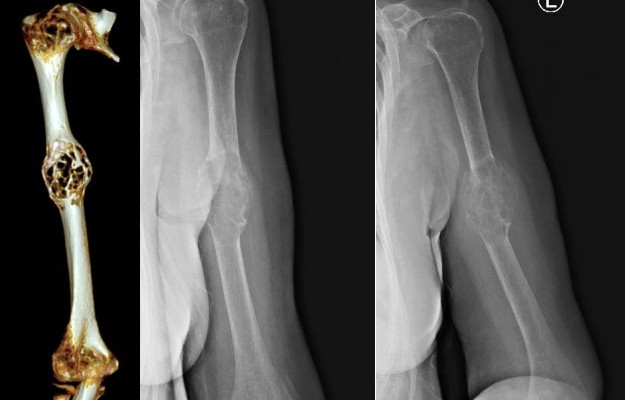

??患者术前影像学检查

??此时的刘阿姨一边饱受着病痛的折磨,一边为即将失去一只手臂感到难过。曹学军充分考虑她渴望保全手臂的意愿后,立即对病情进行了全方位的评估,分析了影像资料。考虑到肿瘤主要集中在肱骨后,曹学军认为完全可以在根治性切除肿瘤的同时,保留肢体形态与功能。经过周密的手术方案设计与术前评估,曹学军最终决定为患者进行高难度的肱骨肿瘤切除+3D定制部分肱骨假体置换手术。

??定制3D人工假体,须做到个性化和精细化的准备。术前,进行了精确的肱骨及肩、肘关节径线、角度的测量。由于部分肱骨置换术难度大,且肱骨周围分布着重要的神经、血管,稍有不慎就会造成患肢血液循环和功能的严重障碍。为了保证患肢功能的恢复,在肱骨肿瘤切除后,还需要进行繁琐的重建程序,尤其要把握好假体放置的各种角度、各组肌腱止点恰当牢固的重建、假体长度的精细调整,以满足术后患肢的功能得到最大程度的恢复。